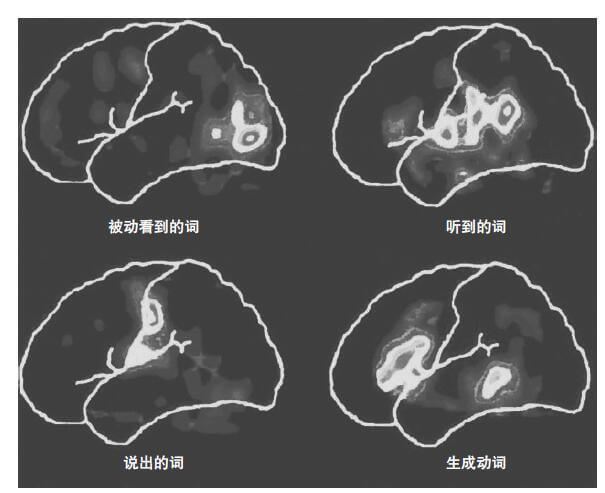

一项新的技术提供了一种克服这些困难的办法。功能性磁共振成像(functional magnetic resonance imaging,fMRI),它所依据的是血液具有磁性的特性。心脏携带的血液磁性最大。而当血液流经毛细血管时,磁性就会减弱。有活动显示的大脑区域,可以表现出血液中含氧和脱氧比例的变化(Banich,2004)。fMRI扫描运用现成的MRI设备,但提供给医生和研究者的是不带伤害、不含辐射地检测不同大脑区域血流情况的方法。图2-5提供的就是一幅fMRI扫描的例子。

这些研究大脑功能运作方式的技术,使得在认知心理学领域产生新联合、引发新问题成为可能。在这些技术出现之前,认知理论是不涉及那些为不同认知加工过程提供保证的生物学机制的。而现在,认知神经科学家依据一种新的假设提出他们的发现:“大脑内部的生理活动及其功能状态之间的映射关系是这样的,如果两种实验条件与不同的神经活动模式相联系,我们就可以认为它们所参与的是不同的认知功能”(Rugg,1997,p.5)。例如,最近一次对275例PET和fMRI研究的回顾总结表明(Cabeza & Nyberg,2000):不同的认知功能如注意、知觉、意象、语言和记忆,所激活的大脑区域是不同的。